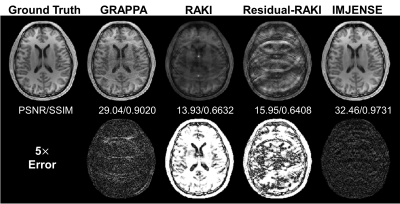

Figure 3 shows the results on the human brain dataset with only 8 ACS lines at R=5. IMJENSE significantly improves the quality of reconstructed images. Quantitatively, IMJENSE achieves the highest PSNR of 32.46 dB and the highest SSIM of 0.9731. Figure 4 plots the PSNR variations of these methods as a function of the number of ACS lines. IMJENSE is more robust to the ACS size.

Figure 3. Comparisons of GRAPPA, RAKI, Residual-RAKI, and IMJENSE on the 32-channel human brain dataset with 8 ACS lines at R=5. Quantitative evaluation metrics are reported below each image. IMJENSE achieves the highest PSNR and SSIM.